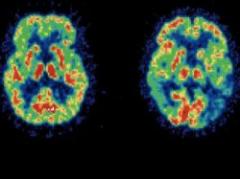

Un estudio realizado con hermanos, unos adictos a las drogas y otros no, ha detectado que ciertas personas tienen unas caracterÃsticas cerebrales que les hace más vulnerables a las dependencias.ver más